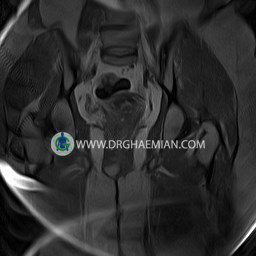

پزشکان اغلب از تصویربرداری ام آر آی برای تشخیص و درمان عارضه های پزشکی که فقط با استفاده از اشعه ایکس یا میدان مغناطیسی و امواج رادیویی قابل مشاهده است، استفاده می کنند. دستگاه ام آر آی تصاویر دقیق از ساختار های داخلی بدن ایجاد می کند. در این کیس کیست بارتولین لگن و تجمع دورمقعدی و کیست ساده ایی در تخمک چپی دیده می شود.

Technique : coronal STIR , coronal T2 , Axial T1 , axial T2 .

The femoral heads and acetabula are normal shape , signal intensity and the femoral heads are well covered by the acetabular margins .

The joint spaces are of normal width without fluid collection .

the articuler surfaces are smooth and congruent and show normal cortical thickness .

there are no marginal osteophytes or subchondral signal changes .

The bone marrow shows normal signal intensity , especially in the femoral head and neck .

Each femoral shaft has normal margins and contains a normal bone marrow signal .

– Simple cyst (28×32mm) in left ovary

– Cyst like lesion (20×25mm) in right vaginal wall suggestive for bartholin cyst and perianal collection

are seen.